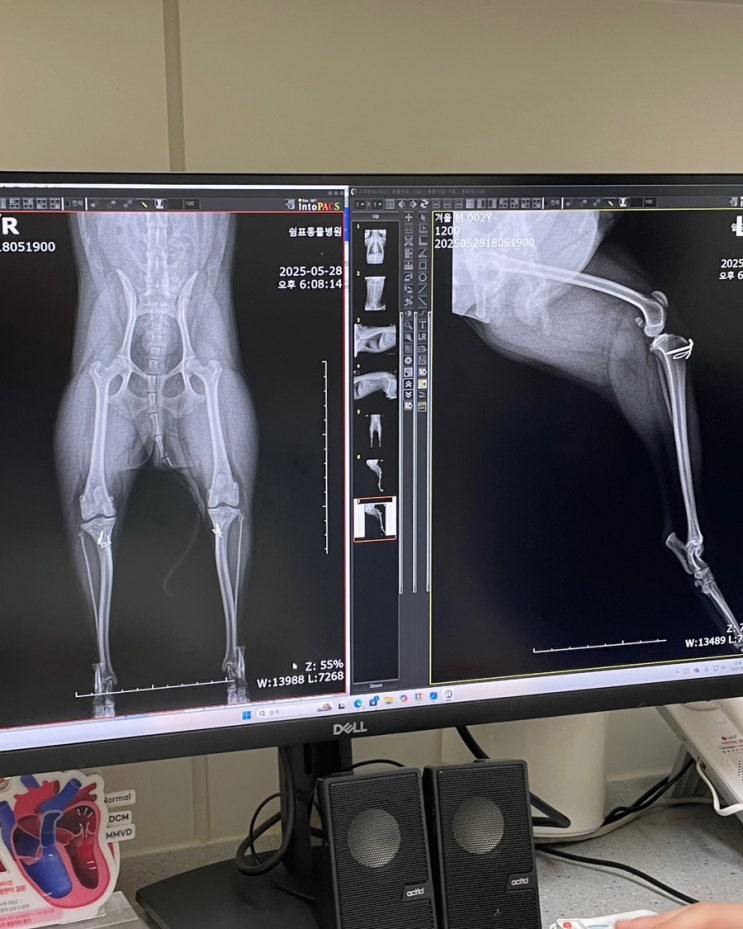

포메라니안 양쪽 슬개골 수술 후 2년

포메라니안 양쪽 슬개골 수술 2년 후기 수의학적 관점에서 슬개골 수술은 예방적 수술이라고 한다. 슬개골 ...